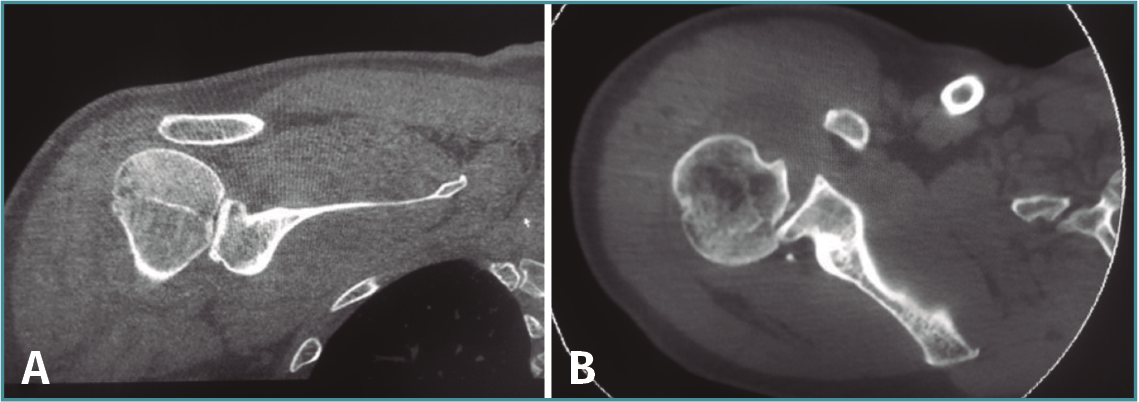

A la exploración física presenta dolor intenso a la palpación e impotencia funcional en el hombro, sin deformidad evidente y con bloqueo de los movimientos rotacionales. Tras realizar radiografías simples en proyecciones anteroposterior e “Y” de escápula (Figura 1), se diagnostica de luxación posterior de hombro.

Figura 1. Radiografía anteroposterior (AP) (A) y proyección en “Y” de escápula (B) donde se objetiva una luxación glenohumeral posterior. En la proyección AP podemos apreciar el clásico signo de la bombilla (light-bulb sign) debido a la rotación interna del brazo.